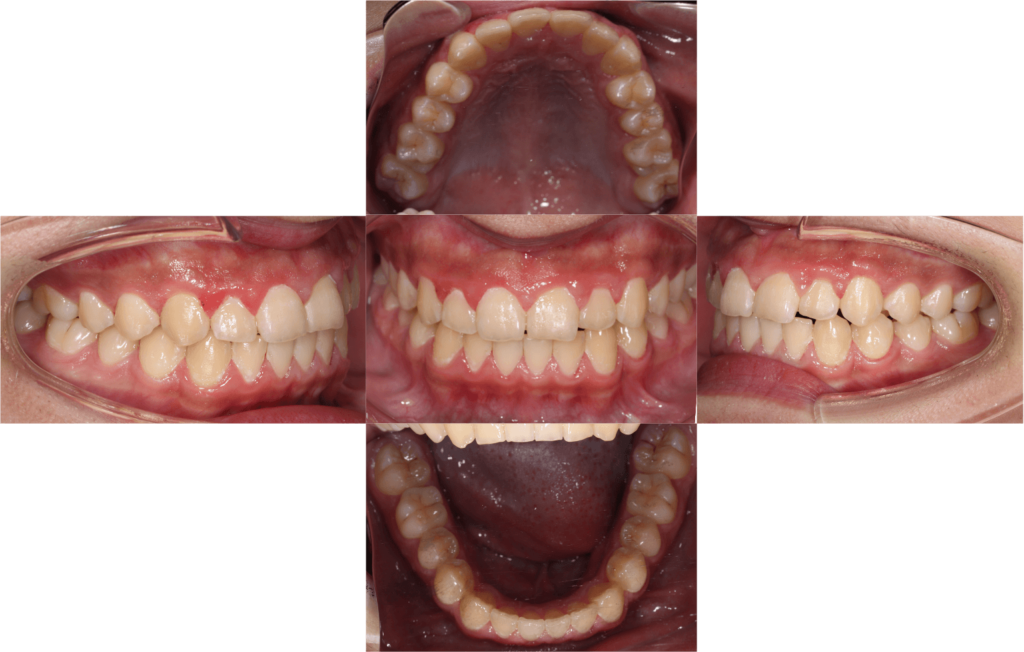

子供の叢生を矯正で改善した症例

患者情報

11歳 男性

主訴

歯並びがデコボコしているのが気になる

診断名

叢生

治療方法

夜間に拡大床を使用

治療期間

2年半

治療のリスク

装置を使わないと治療が進まず、叢生が改善しない

費用

検査:44,000円(税込)

装置:385,000円(税込)

再診料:5,500円×8回=44,000円(税込)